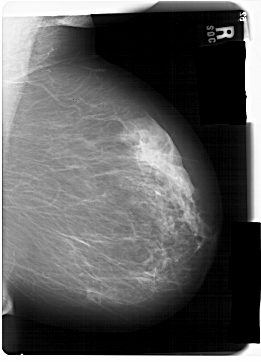

A_1466_1.LEFT_MLO

LEFT_MLO LINES 6871 PIXELS_PER_LINE 5041 BITS_PER_PIXEL 12 RESOLUTION 43.5 OVERLAY